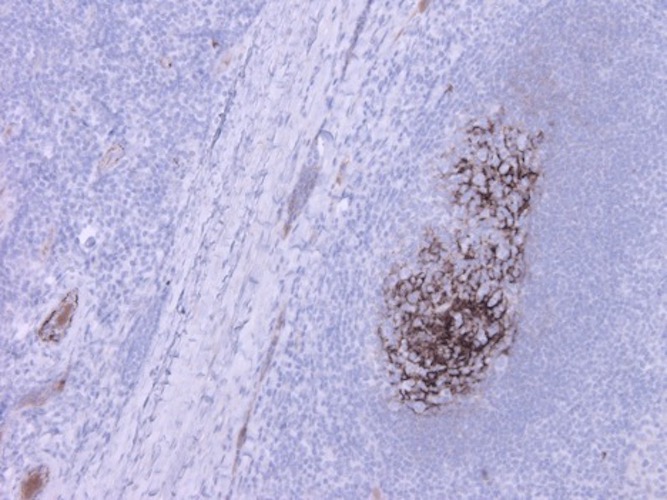

IHC staining of tonsil tissue with ABS 004-22. Follicular dendritic cell network stained strongly in germinal centers of tonsil tissue. Also moderate staining were observed from plasma of veins. Dilution: 1:100.